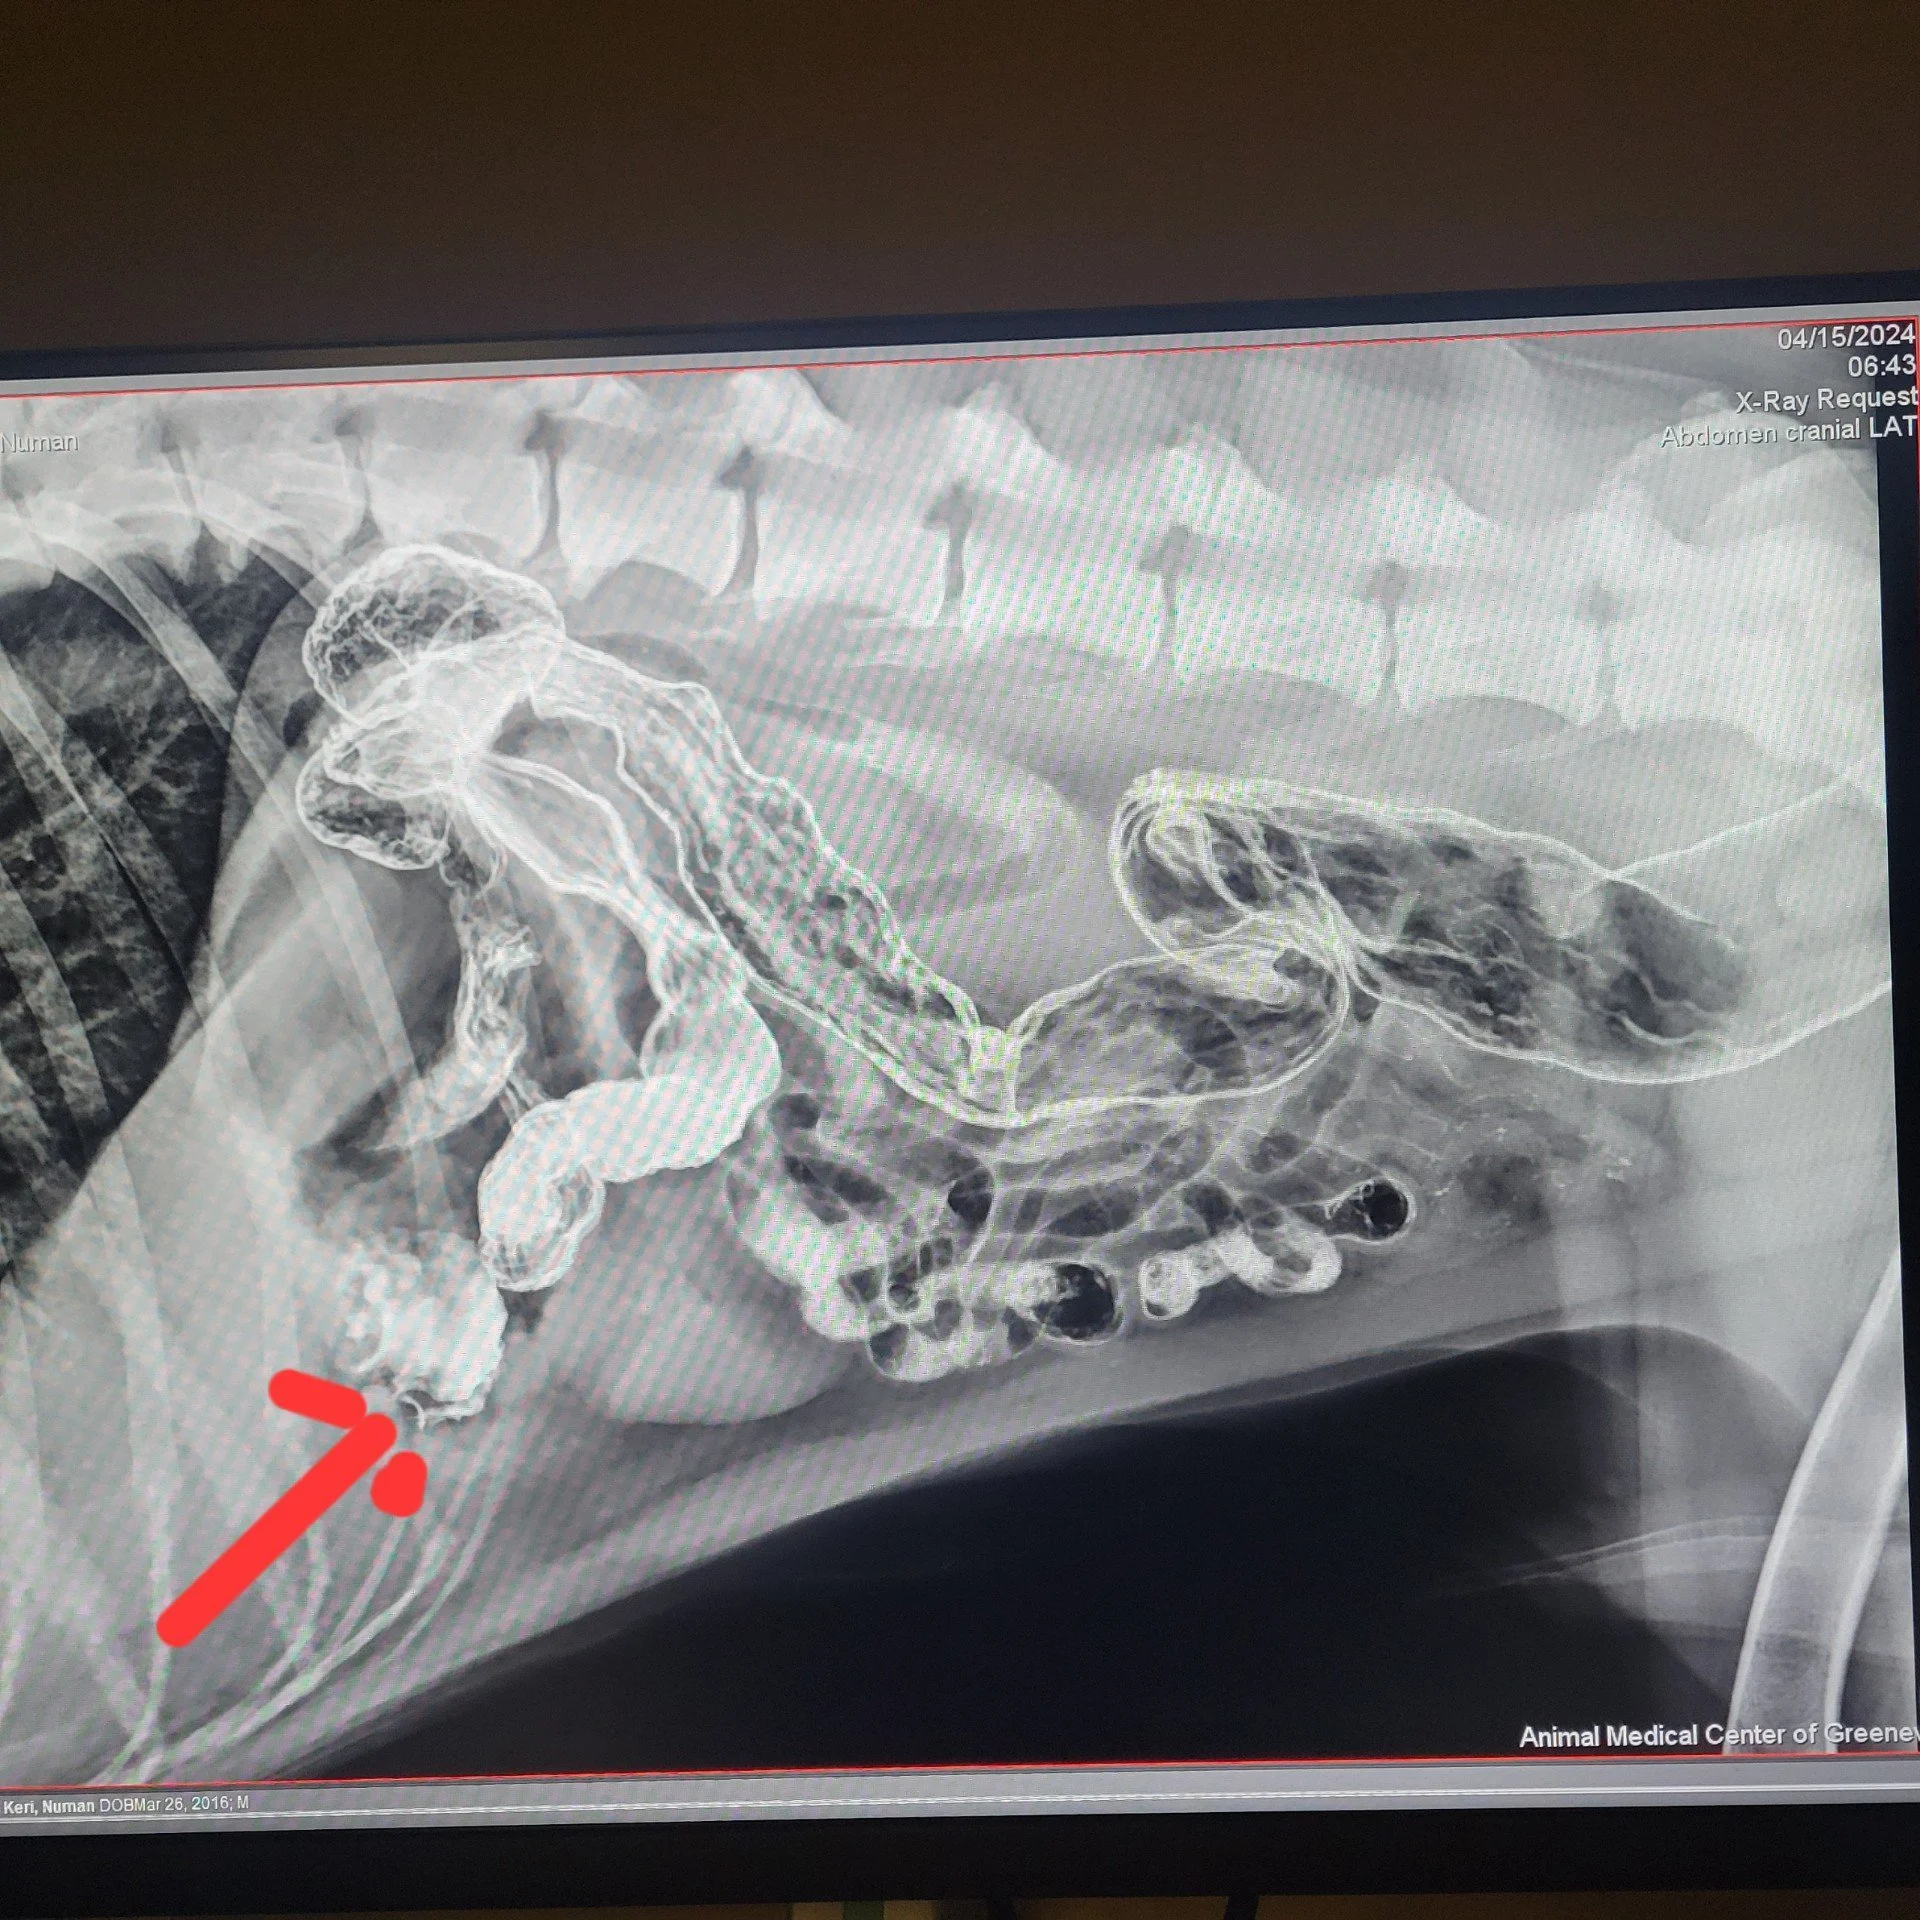

When we arrived at the Animal Medical Center of Greeneville, the staff were ready for us. We went straight into a room where Dr. J and Dr. Al examined the little dog with urgency and great care. “This little girl has been through a lot of trauma.” Dr. J stated bluntly. They immediately prepped her for an X-ray.

Dr. J was able to determine Sheila’s ribs had already begun to heal, and while her heart was a bit close to her sternum, her lungs and other vital organs were okay.